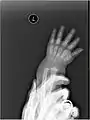

X-ray image of right hand with thumb on left.

Multiple fractures of the metacarpals (aka broken hand). (Right hand shown with thumb on left.)

X-ray image of human infant left hand.